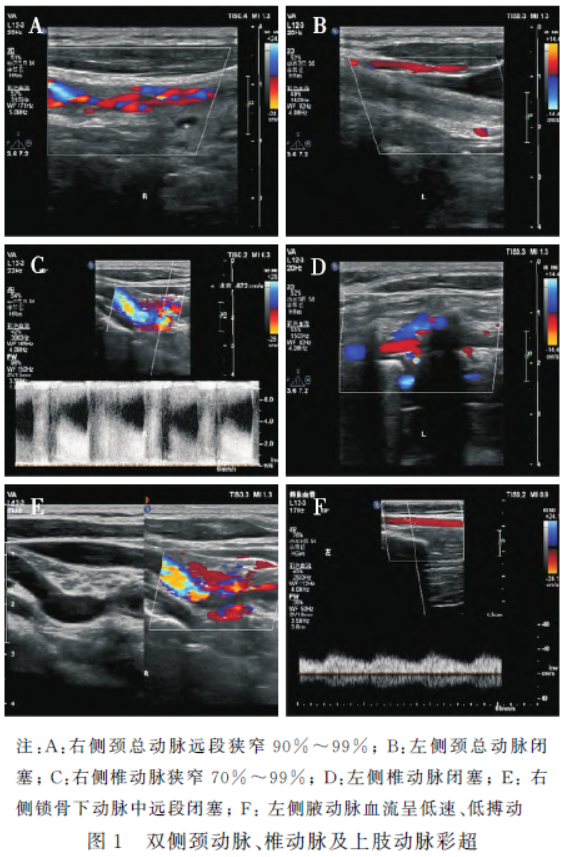

双侧颈动脉及椎动脉彩超示(图1):右侧颈总动脉狭窄(节段性;远段90%~99%);左侧颈总动脉闭塞(全程);双侧颈外动脉向颈内动脉供血;右侧椎动脉狭窄(V1段开口处:70%~99%);左侧椎动脉闭塞(V1段),左侧椎动脉全程细(生理性);右侧锁骨下动脉闭塞(中远段),左侧锁骨下动脉闭塞(全程)。双侧上肢动脉彩超示:右侧锁骨下动脉闭塞(中远段),左侧锁骨下动脉闭塞(全程)。

头臂干型大动脉炎患者最常见症状为双侧上肢无脉或脉搏不对称,此外,可出现头痛眩晕、脑卒中等神经系统表现,少数患者可发生视力异常。本例患者主要表现为进行性加重的头昏、双侧视力减退、视野缺损等脑灌注不足症状,辅助检查结果提示患者主动脉弓以上大血管狭窄程度异常严重,对头部供血的颈动脉及椎动脉均严重狭窄或闭塞(左侧颈总动脉及左侧椎动脉完全闭塞,右侧颈总动脉及右侧椎动脉狭窄最严重程度达99%),仅依靠侧支循环供血。因此,该患者头部供血的血管狭窄程度较一般头臂干型大动脉炎更为严重,实属罕见。